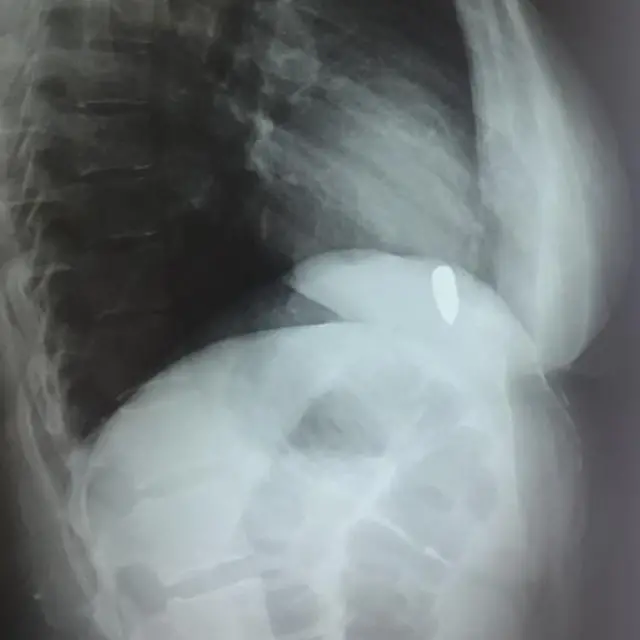

ఆరు నెలలుగా ఓ మహిళ ఛాతీలో చిక్కుకున్న తుపాకీ గుండును ఆపరేషన్ చేసి బయటకు తీశారు డాక్టర్లు. ఇంతకూ ఆమె గుండెలో ఆ బుల్లెట్ ఎక్కడ దాక్కుందో డాక్టర్లకు అంతుచిక్కలేదు. దీన్నే బ్లైండ్ బుల్లెట్ అంటారు.

నాజియా గుండెను చేత్తో తాకినప్పుడే బుల్లెట్ గుండెకు అతుక్కుని ఉందని గ్రహించాను. ఎక్స్ రే తీసినప్పుడు గుండెతో పాటూ బుల్లెట్ కూడా పైకి కిందకు కదలడం గమనించాం. ఆరు నెలలుగా గుండెలో బుల్లెట్తో ఆమె ఎంతో బాధపడ్డారు. సర్జరీ కోసం ఉపక్రమించి ఛాతీ తెరిచాక ఆమె గురించి చాలా అందోళన కలిగింది.

"అల్లాను తలుచుకుని, మెల్లిగా కుడివైపు హృదయకుహరం (వెట్రికల్) వైపుకు జరిగాం. అక్కడే బుల్లెట్ గుండెను అతుక్కుని ఉంది. కార్డియాక్ సర్జన్లు ఒక మెషిన్ ద్వారా రోగి గుండెను నియంత్రిస్తారు. కానీ నా దగ్గర అలాంటి సాధనాలేమీ లేవు. ఆమె గుండె కొట్టుకుంటూ ఉండగానే సర్జరీ చేయాల్సి వచ్చింది. గుండె కొట్టుకుంటున్నప్పుడు అతి చిన్న పొరపాటు కూడా పెద్ద ప్రమాదానికి దారి తీయవచ్చు. అక్కడ చాలా సున్నితమైన సిరలు ఉంటాయి.

రెండుసార్లు బుల్లెట్ను సమీపించేందుకు ప్రయత్నించాం. కానీ, అది చిక్కలేదు. మూడోసారి విజయం సాధించాం" అని డాక్టర్ జాహిద్ వివరించారు.

"బుల్లెట్ తొలగించిన తరువాత రోగి రక్తపోటు 15 సెకెండ్ల పాటూ పూర్తిగా పడిపోయింది. అప్పుడు ఒక పెద్ద సంచీడు రక్తం బయటకు పొంగింది. ఆ 15 సెకెండ్లు అత్యంత ప్రమాదకరమైన క్షణాలు.

గుండె కొట్టుకోవడానికి చేయాల్సిన ప్రయత్నాలన్నీ చేశాం. తరువాత మరో 20 సెకెండ్లకు రోగి పరిస్థితి మెరుగుపడింది. ఆరునెలల పాటు గుండెలో బుల్లెట్తో బాధపడిన ఆమె ప్రాణం నిలబడిందని ఊపిరి పీల్చుకున్నాం" అని డాక్టర్ జాహిద్ తెలిపారు.